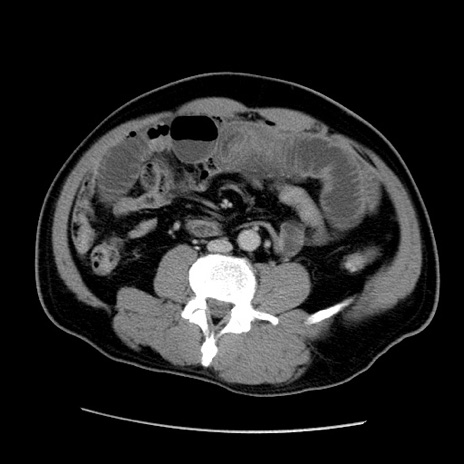

冠状断像

【症例】50歳代男性

【主訴】腹痛

【現病歴】AVMからの被殻出血のため回復期リハ病棟入院中。 本日午後3時頃急に下腹部痛が出現した。

【既往歴】AVM、被殻出血、虫垂炎、高血圧

【身体所見】意識晴明、左半身不全麻痺、会話の理解は良好、36.5°C、腹部:膨隆、全体に板状硬、下腹部正中に圧痛点あり、反跳痛-、筋性防御不明、右下腹部にope scar

【データ】WBC 9400、CRP 0.06